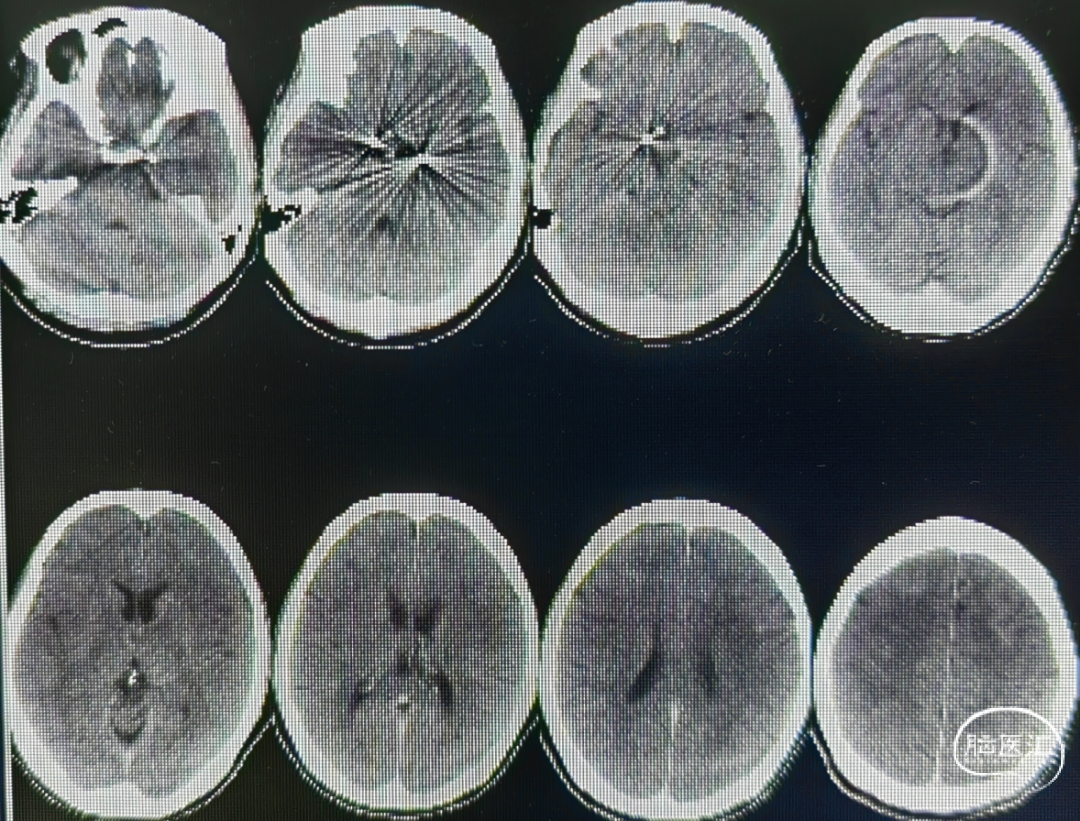

术前影像

病例诊断:颅内多发动脉瘤

1.左侧大脑前动脉A1起始部未破裂动脉瘤(囊性)

2.右侧大脑前动脉A1起始部未破裂动脉瘤(夹层)

术后情况

术后检查:

术后麻醉苏醒顺利,生命体征平稳,神志清楚,对答流利,双侧瞳孔等大等圆,直径3.0mm反射灵敏,四肢活动良好。